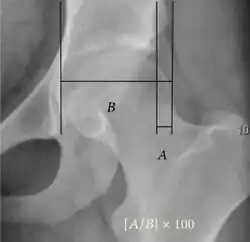

| Acetabular depth ratio | ![]() |

Deepness of acetabulum. | >250

|